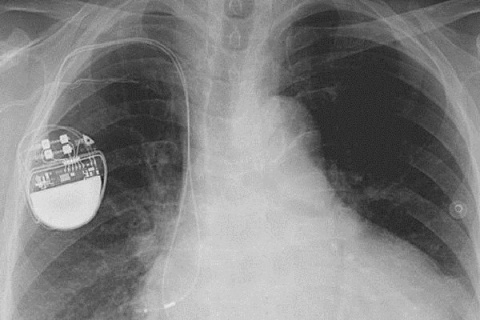

کارشناسان امنیتی هشدار می دهند که هکرها می توانند با نفوذ به دستگاه های تنظیم ضربان قلب که در داخل بدن انسان کار گذاشته می شود، زندگی این بیماران را به خطر بیندازند.

به گزارش سیتنا به نقل از گیزمودو، بسیاری از تجهیزات پزشکی مبتنی بر فناوری اطلاعات مانند پمپ های تزریق انسولین و دستگاه های تنظیم کننده ضربان قلب از آسیب پذیری هایی برخوردار هستند که دستکاری آنها برای هکرها را ممکن می کند.

محققان شرکت امنیتی وایت اسکوپ می گویند دستگاه های تنظیم ضربان قلب ۴ شرکت مشهور سازنده این نوع تجهیزات و همین طور سیستم های مورد استفاده برای کنترل و بررسی عملکرد دستگاه های یاد شده در مجموع دارای ۸۰۰۰ آسیب پذیری مختلف هستند و این تعداد بی سابقه از اشکالات بسیار نگران کننده است.

کارشناسان وایت اسکوپ می گویند سیستم های نرم افزاری تولیدات هر چهار شرکت قدیمی و به روز نشده بوده و اطلاعات خصوصی مربوط به هر بیمار به طور رمزگذاری نشده بر روی آنها ذخیره می شود. لذا در زمان اتصال آنها به سیستم های نظارتی بدون نیاز به ورود کلمه عبور می توان به این اطلاعات دسترسی پیدا کرد.

این اولین بار نیست که هشدارهایی در مورد امنیت پایین تجهیزات حساس پزشکی منتشر می شود. در سال ۲۰۱۳ هم هکری به نام بارنابی جک از فاصله ۱۵ متری توانسته بود شوکی مرگبار به یک دستگاه کنترل ضربان قلب وارد کند، اما شرکت های سازنده این نوع تجهیزات هشدارهای یاد شده را جدی نمی گیرند.